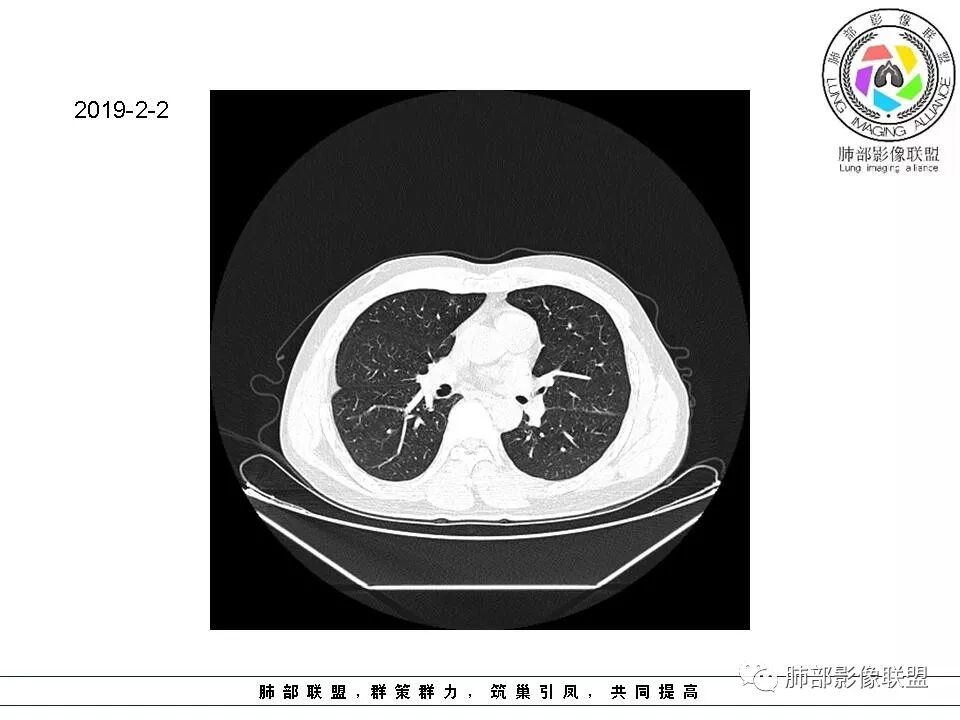

群内讨论

杨泽锋:很难通过一次CT检查来判断小结节的性质炎性结节可能大理由:病灶很小但是很密实毛刺比较长百事可乐:右肺中叶内侧段实性小结节,毛刺、分叶,胸膜牵拉。考虑MIA。李:实性结节,形态不规则,考虑炎性肉芽肿紫气东来:右肺中叶实性结节,毛刺分叶,考虑恶性。穿越七海的风:右肺上叶近胸膜下小结节,实性度较高,肺内淋巴结吧,可随访观察张帅:晨读,右肺上叶前段小结节病变,病灶内可见细支气管穿过,局部血管略增粗,病灶边界清,可见软毛刺,3月胸CT较2月貌似密度减低,毛刺变小,考虑良性病变,炎性病变?春秋:患者51男性,右上叶前段结节,形态不规整,明显分叶,前后变化不明显,考虑恶性!Yiren  Sishui(厶水伊人):小结节,密度较实,有多条线状影,胸膜下分布,肺内淋巴结?炎性肉芽肿?建议随访。东哥:晨读:右肺上叶小结节,不规则,可见分叶,整体收缩,两次CT变化不明显,先考虑良性可能我心飞翔:右上肺实性结节,长毛刺,考虑良性病变王秀仙:晨读:右肺上叶结节,边缘毛刺,一个月后,病灶略有增大,边缘小叶间隔阻挡,考虑腺癌。Shelia🌞:晨读,右肺上叶前段胸膜下小结节,形态不规则,以平直收缩为主,可见u型凹陷,长毛刺,1月复查感觉变化不大,考虑炎性病变,建议继续随访复查除外腺癌一切∮随缘:晨读病例:     右肺上叶前段可见一不规则结节,边缘可见分叶,毛刺,清晰的GGO,近端牵拉血管树,未见明显支气管截断,中年男性,体检发现,综合考虑微浸润腺癌,待排炎性肉芽肿,建议短期随访。

Ao..葉偲雨!👑:右肺中叶内侧段小结节,边缘毛刺,部分层面平直,第二次复查有凹陷,密度似乎比之前淡泊一点(肿瘤的生长周期一个月一般不会有太多变化),大小范围基本稳定,LU-Rads 4a类,炎性结节可能,建议3个月后复查或pet

南边:51岁男性,体检发现右肺结节这个年龄段的男性,啥都可以发生,也属于肺癌的高危人群南边:首先是实性还是GGO?好像实性吧

如果实性病变,边缘收缩,可以考虑炎性, 但是边缘有边界清楚GGO,一定要警惕恶性,还有粗短毛刺更要小心撇开其它,看到这个图,除非你怀疑假象,不然就是要考虑腺癌的可能

边界清楚GGO,短毛刺,这要小心瘢痕癌可以多为腺癌复查没变化,与血供有关,属于休眠期张国祯教授的理论:腺瘤样增生、原位癌都属于偏良性,就是没有侵袭性;以后发展——侵袭可以,不变可以,部分可能还会凋亡(比较少)

结果

原位腺癌